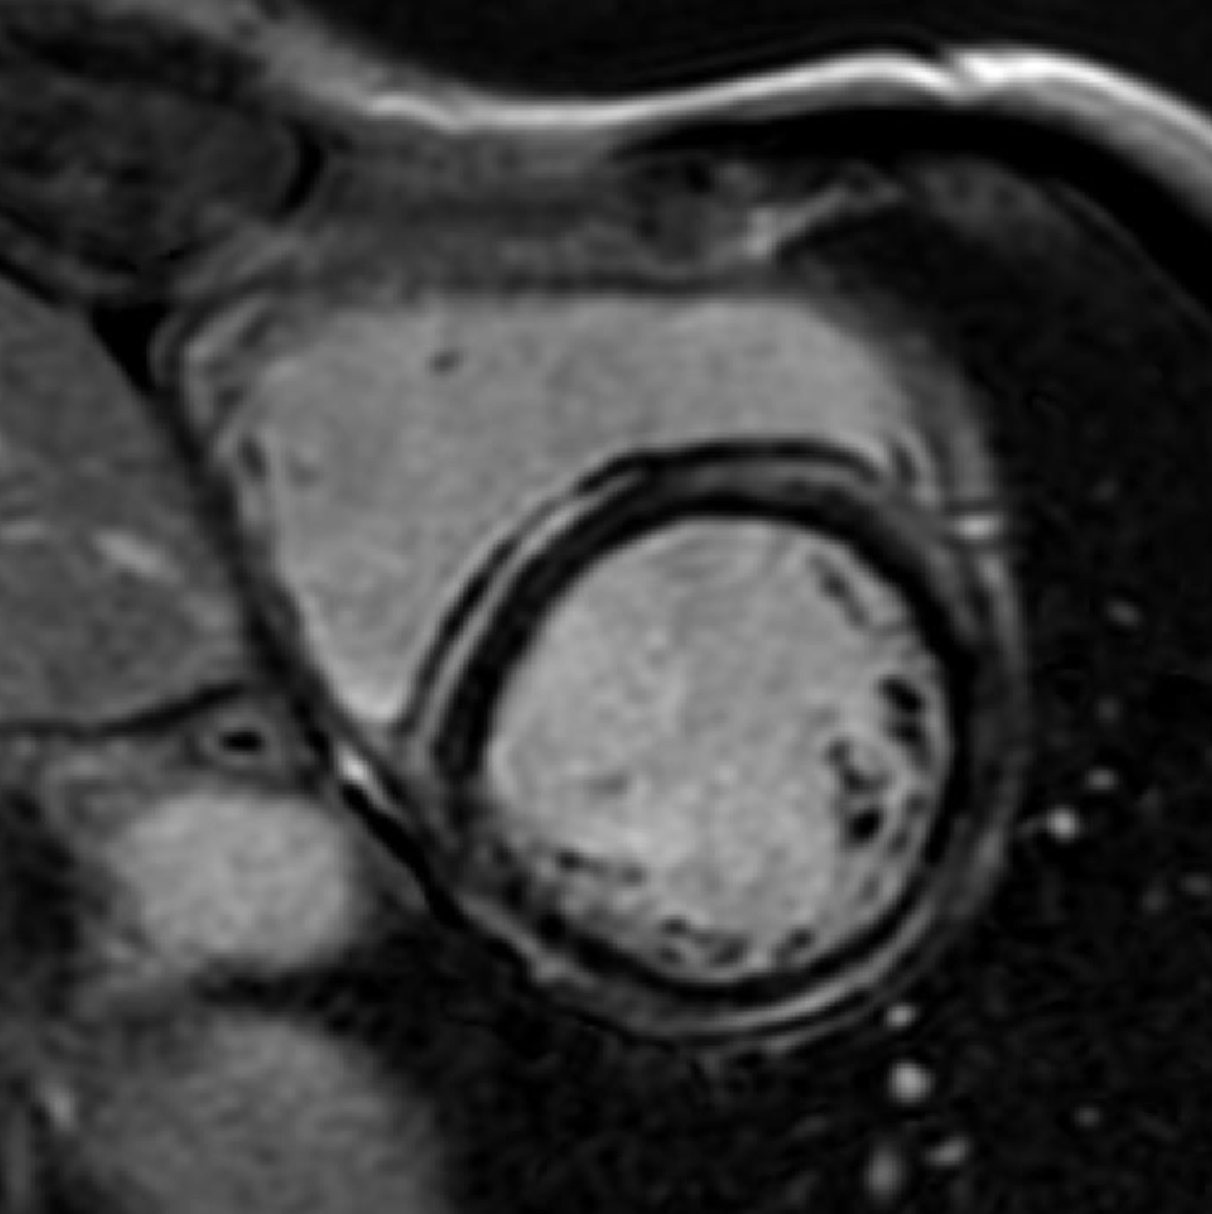

There is a world outside the stent mesh

Caso condiviso da Saima Mushtaq

Paziente con anamnesi di malattia coronarica e pregresso impianto di stent sulla discendente anteriore sinistra.

Per prima cosa, esamina l'intera scansione. Concentrati sul tronco comune e sulla porzione prossimale della discendente anteriore sinistra.